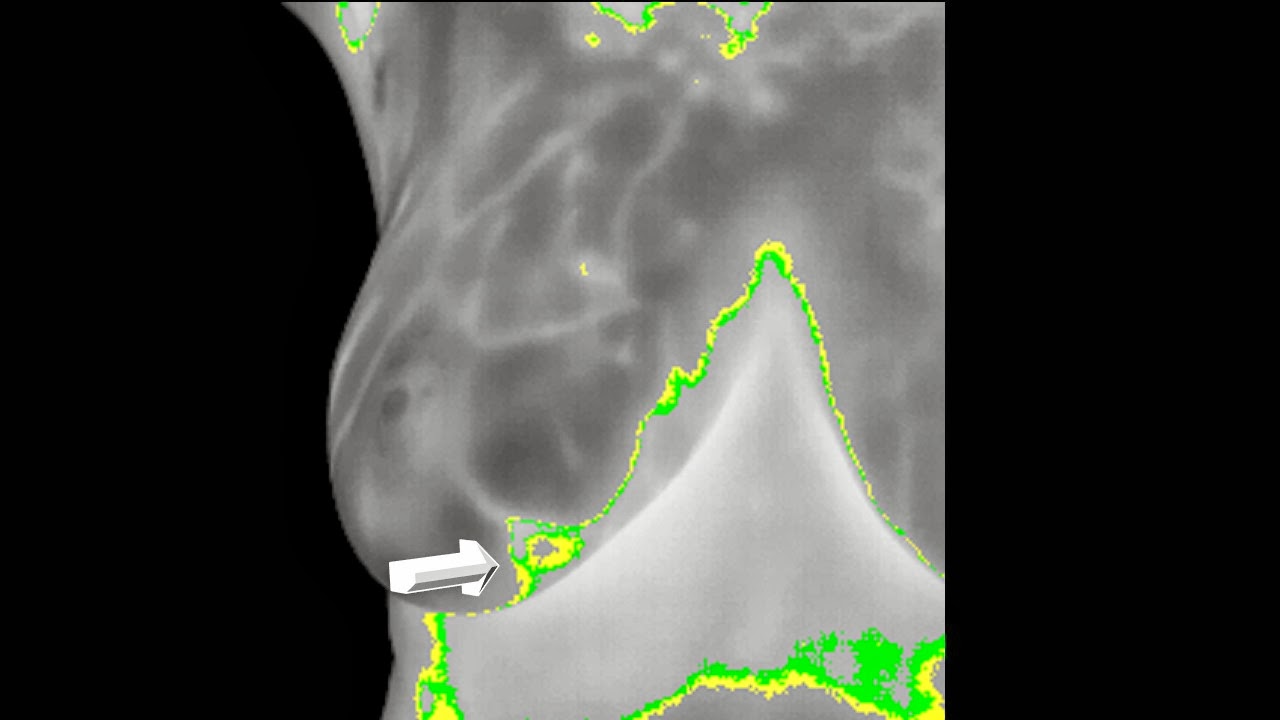

Proyección Anterior Basal :

La radiación infrarroja es mas Obvia en el lado Izquierdo : El Surco Mamario irregular , la trama vascular , el predominio del calor emitido en el lado izquierdo y la presencia de una Hipertermia Única y coincidente con el Nódulo Palpable.

Pero en el Lado derecho en su CUADRANTE SUPERO EXTERNO existe también una Hipertermia Aislada que clinicamente coincide con el área de las microcalcificaciones no sospechosas para mi compañero radiólogo .

La serie Fisiológica después del estimulo en frío : persistencia de esta Hipertermia única.